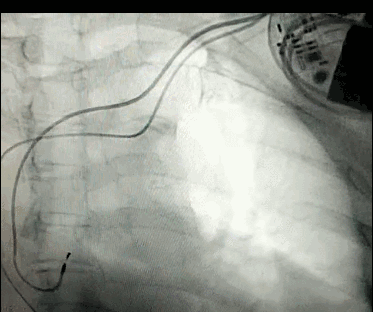

DSA是將造影劑注入需要檢查的血管中,使血管顯露原形,然后通過系統(tǒng)處理,使血管顯示更加清晰,便于醫(yī)生診斷或進(jìn)行手術(shù)。